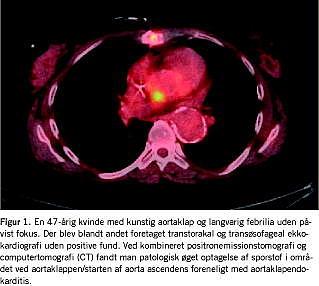

Feber af ukendt årsag

Feber af ukendt årsag (FUO) kan være en klinisk og diagnostisk udfordring (Figur 1 ). Tilstanden blev første gang defineret i 1961 af Robert G. Petersdorf et al som febrilia over 38,3 °C ved mindst to lejligheder i en periode på 2-3 uger og uafklaret diagnose efter en uges indlæggelse. Sidstnævnte er siden revideret til manglende diagnose trods passende udredning. Populært angives det, at de mulige årsager kan være infektion, okkult malign lidelse og autoimmun inflammatorisk systemsygdom med omtrent samme hyppighed, men i op mod en tredjedel af tilfældene stilles en endelig diagnose ikke trods omfattende udredning. FDG PET giver mulighed for helkropsskanning med et sporstof, der potentielt akkumuleres i alle tre tilfælde, hvorfor sensitiviteten teoretisk set er høj, mens specificiteten er tilsvarende begrænset [1]. Dette kan dog opfattes positivt, idet udredningens primære formål er at påvise og lokalisere uanset ætiologi. Der er kun publiceret seks studier med FDG PET (n = 16-74), som er samlet i en nyere oversigtsartikel [1]. Selvom studiedesign, patientpopulationer og resultatopgørelse er varierende, synes resultaterne lovende: PET bidrog positivt til diagnosen i 25-87% af tilfældene, og teknikken spås et betydeligt potentiale, specielt i kombination med CT. En særlig fordel ved kombineret FDG PET/CT er, at man opnår informationerne med en enkelt undersøgelse i modsætning til den gængse diagnostiske strategi, der ofte involverer en række forskellige modaliteter, der er fordelt på flere undersøgelsesdage.